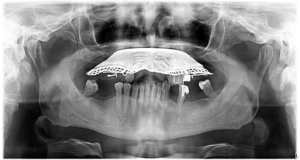

În 2023  Domnul P. s-a hotărât să își recapete zâmbetul, afectat de multiple complicații de-a lungul anilor.  Acesta purta o proteză mobilă ce îi îngreuna atât viața socială, cât și procesul masticator și, implicit, și cel digestiv.Domnul P. ne-a mărturisit că nu știa cum își poate recăpăta sănătatea dentară, deși căutase multe variante, așa că s-a bucurat enorm când a ajuns în clinica noastră. În urma consultației inițiale am redactat un plan de tratament personalizat pentru situația sa dentară, ce cuprindea:

• Inserarea a 6 implanturi dentare la maxilar

• Inserarea a 6 implanturi dentare la mandibula